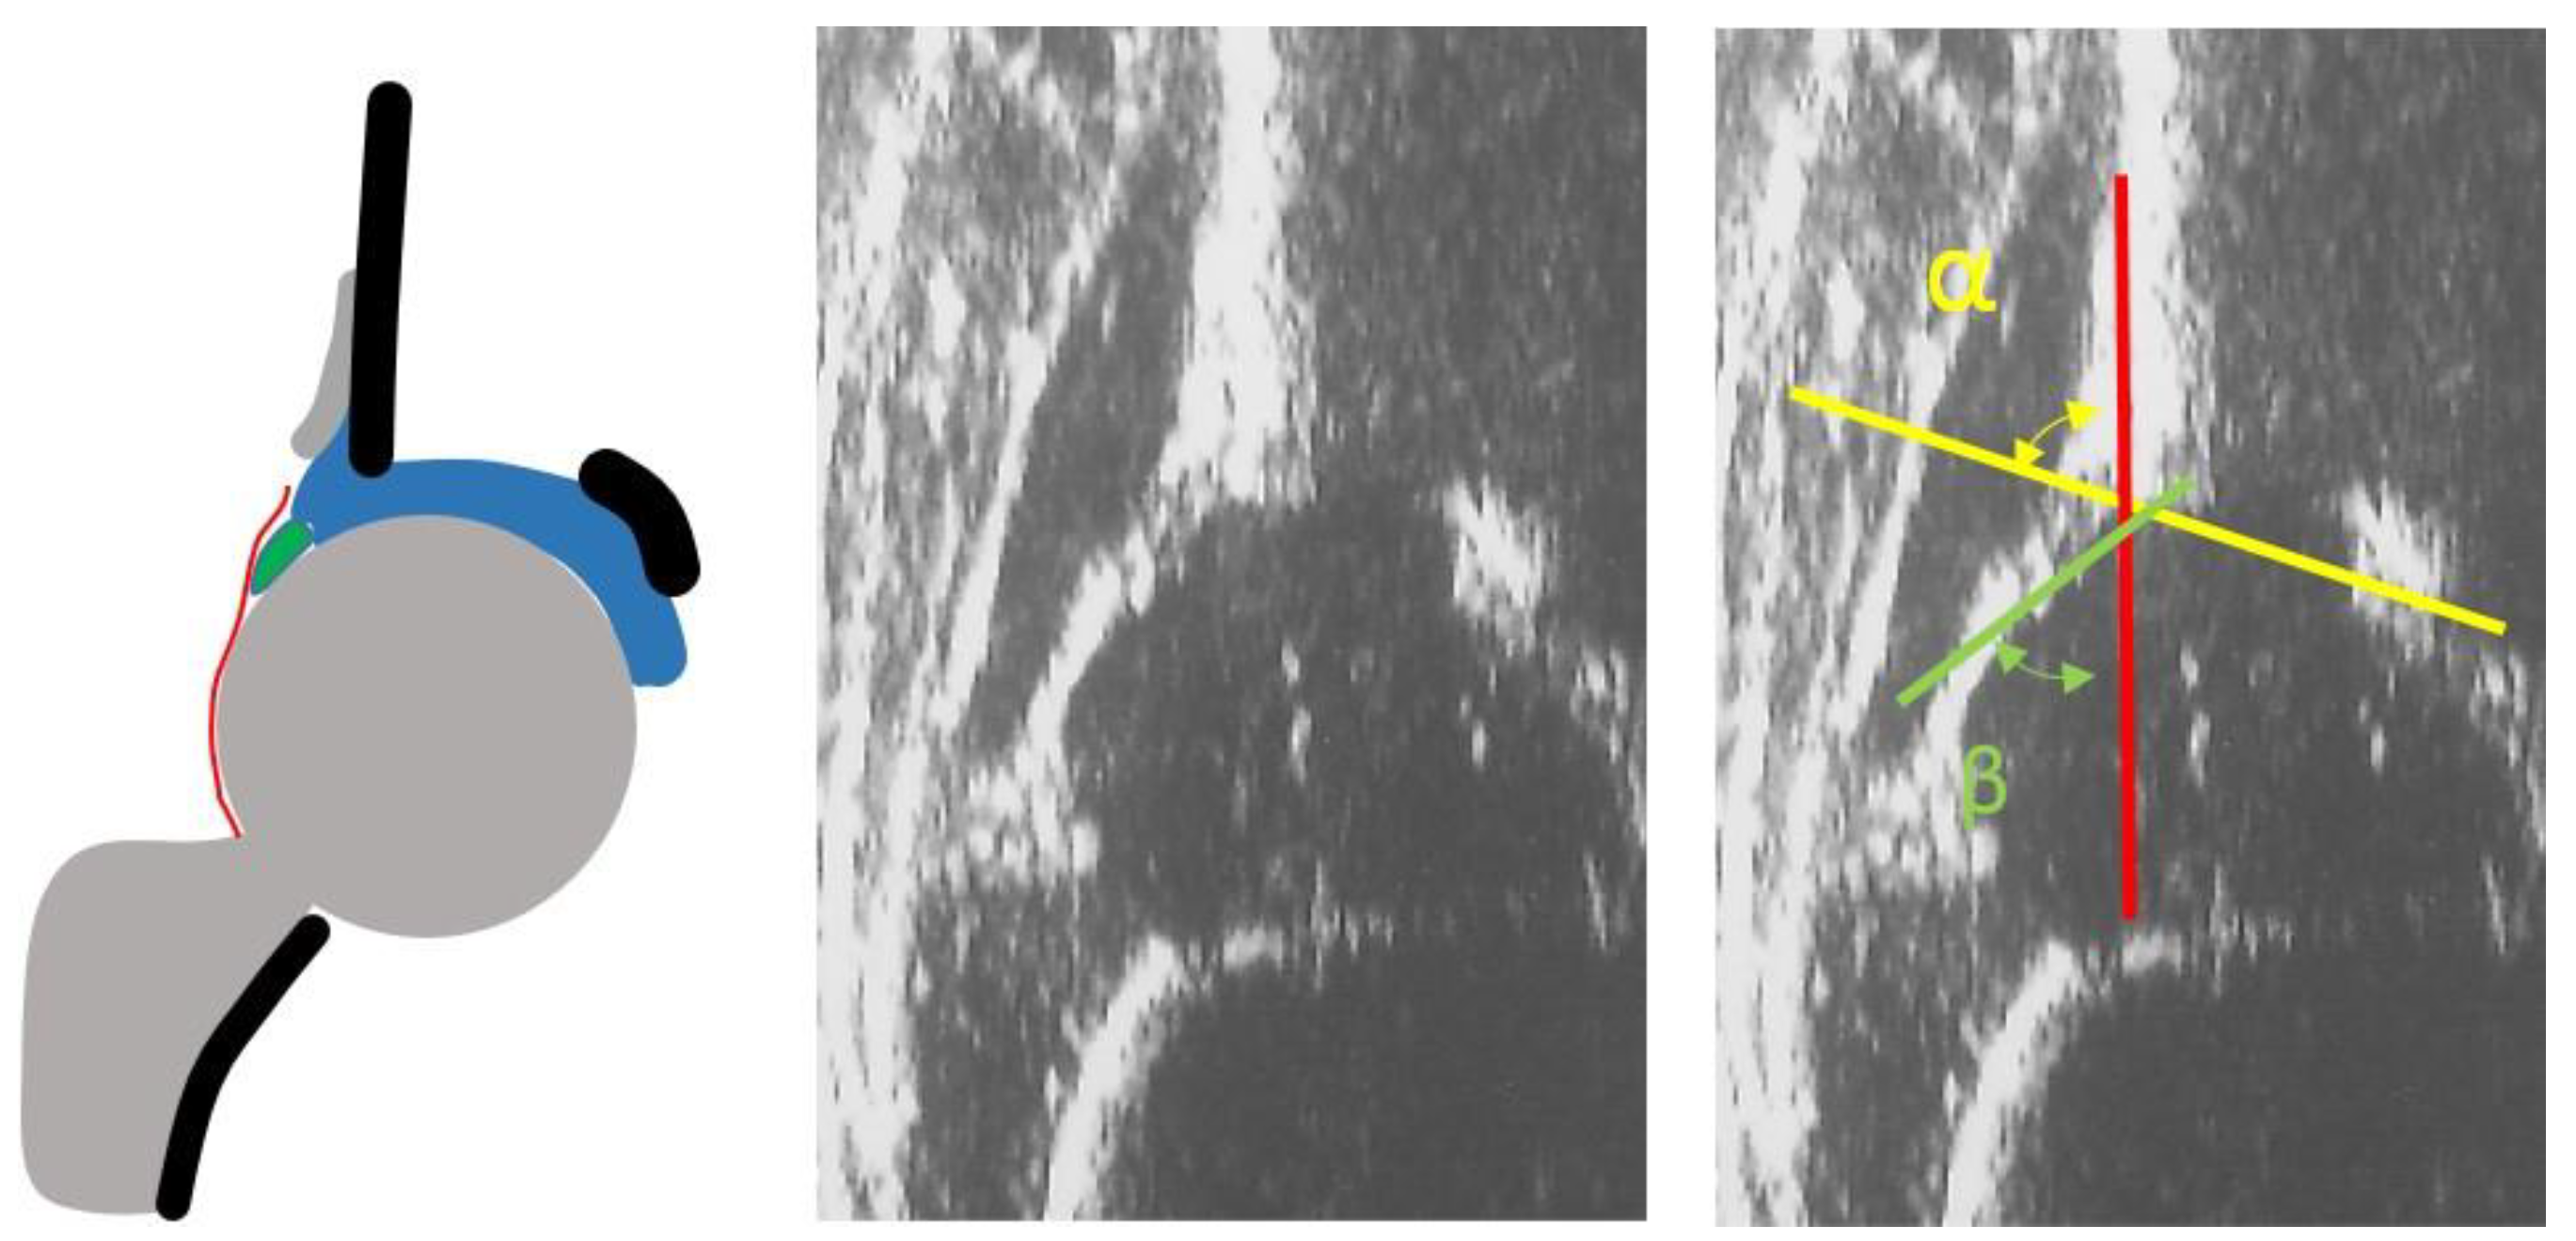

- infants with type I hips at the US examination according to Graf classification (Figure 1)